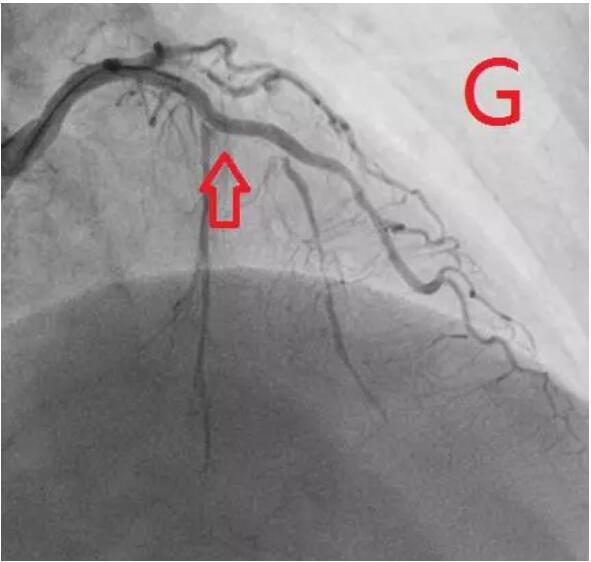

对冠状动脉造影及IVUS图像进行综合判断,目前已经具备安全进行冠状动脉支架治疗的条件,于是在病变处植入支架治疗,随后在IVUS指导下采用后扩球囊改善贴壁情况,顺利完成手术(图G、H)。